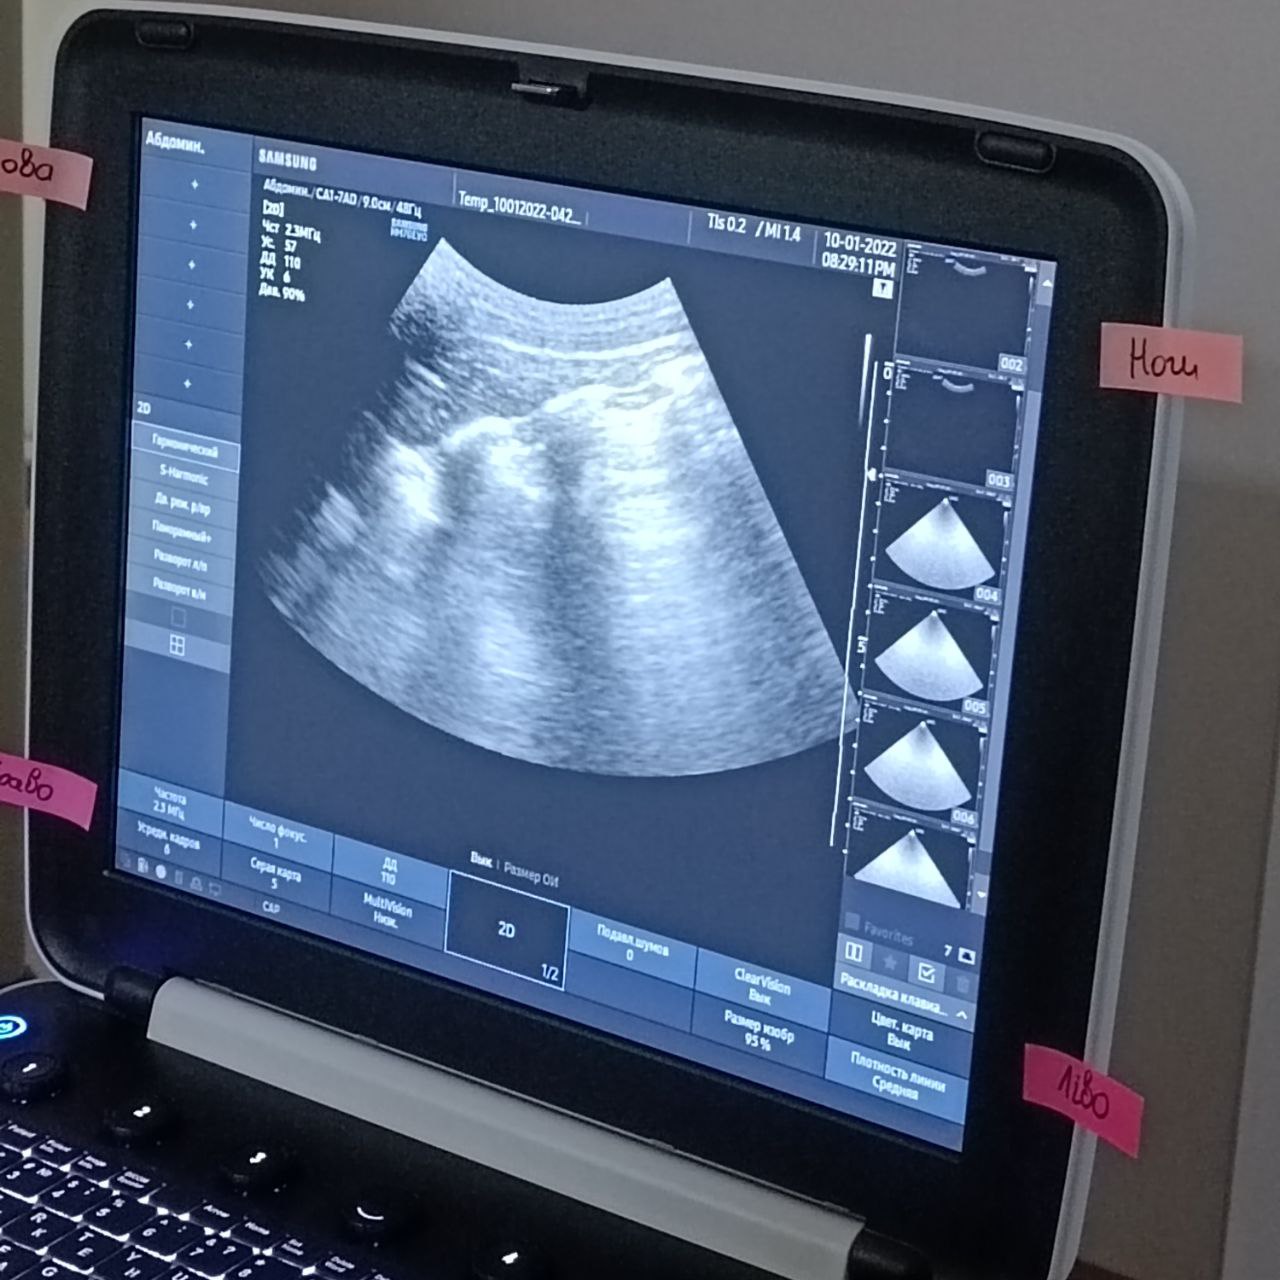

З 5 по 6 листопада 2022 року в Тренінг центрі "Center of Surgical Innovation ®" відбувся тренінг з оволодінням практичних навичок «Просунутий курс ультразвукової діагностики в інтенсивній терапії».

Під час курсу учасники оволоділи:

1)Освоєння моніторингу гемодинаміки в інтенсивній терапії;

2)Оцінка внутрішньосерцевої гемодинаміки - клапанна патологія, робота з кольоровим доплером, CW, PW-доплером;

3)Оцінка IVC, залежність від клінічної ситуації - ХОЗЛ, РДС, ШВЛ;

4)УЗД-супровід пацієнтів з важким ОРДС;

5)Протоколи RUSH, GUCCI. УЗД під час СЛР, відпрацювання командної взаємодії.